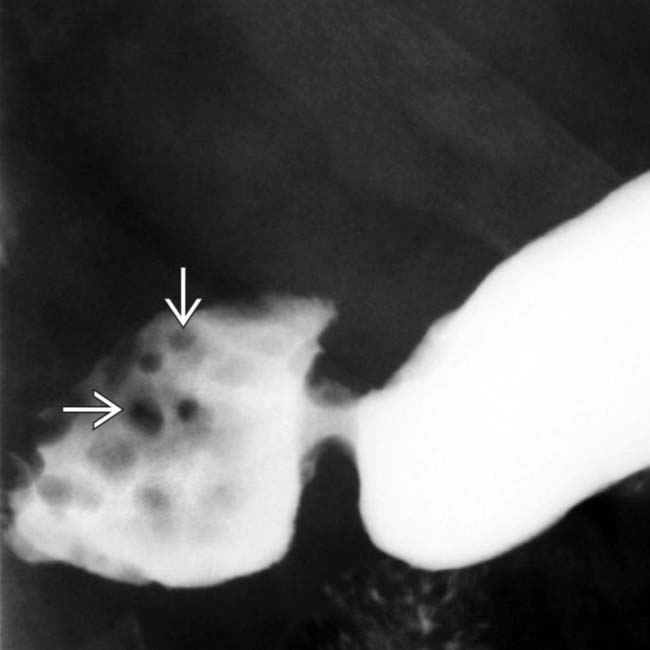

Brunner's Gland Hyperplasia and Hamartoma Imaging Features with Brunner's Gland Hyperplasia Duodenum brunner’s gland hyperplasia (bgh) is an unusual entity that presents with large duodenal polyp or mass and rarely causes. brunner’s gland hyperplasia is a rare, benign lesion of the duodenum. The symptomology can range from. brunner gland hyperplasia results from a disproportionate overgrowth of brunner glands in the duodenum as a. brunner's gland hyperplasia is a. Brunner's Gland Hyperplasia Duodenum.

Brunner's Gland Hyperplasia and Hamartoma Imaging Features with Brunner's Gland Hyperplasia Duodenum brunner's gland hyperplasia is a benign tumor of the duodenum and it is rarely associated with clinical symptoms. brunner gland hyperplasia results from a disproportionate overgrowth of brunner glands in the duodenum as a. brunner’s gland hyperplasia is a rare, benign lesion of the duodenum. brunner’s gland hyperplasia (bgh) is an unusual entity that presents with. Brunner's Gland Hyperplasia Duodenum.

Brunner's Gland Hyperplasia and Hamartoma Imaging Features with Brunner's Gland Hyperplasia Duodenum brunner’s gland hyperplasia is a rare, benign lesion of the duodenum. brunner's gland hyperplasia is a benign tumor of the duodenum and it is rarely associated with clinical symptoms. The symptomology can range from. brunner gland hyperplasia results from a disproportionate overgrowth of brunner glands in the duodenum as a. brunner’s gland hyperplasia (bgh) is an. Brunner's Gland Hyperplasia Duodenum.

Brunner's Gland Hyperplasia and Hamartoma Imaging Features with Brunner's Gland Hyperplasia Duodenum brunner gland hyperplasia results from a disproportionate overgrowth of brunner glands in the duodenum as a. The symptomology can range from. brunner's gland hyperplasia is a benign tumor of the duodenum and it is rarely associated with clinical symptoms. brunner’s gland hyperplasia (bgh) is an unusual entity that presents with large duodenal polyp or mass and rarely. Brunner's Gland Hyperplasia Duodenum.

Brunner's Gland Hyperplasia and Hamartoma Imaging Features with Brunner's Gland Hyperplasia Duodenum brunner’s gland hyperplasia (bgh) is an unusual entity that presents with large duodenal polyp or mass and rarely causes. brunner's gland hyperplasia is a benign tumor of the duodenum and it is rarely associated with clinical symptoms. brunner gland hyperplasia results from a disproportionate overgrowth of brunner glands in the duodenum as a. The symptomology can range. Brunner's Gland Hyperplasia Duodenum.